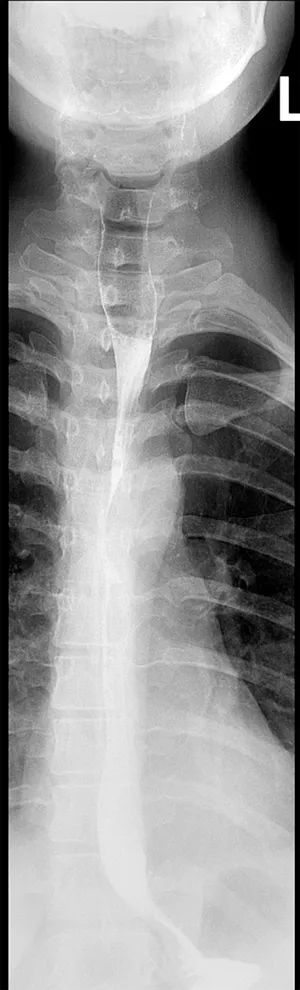

Digitale Durchleuchtung

Röntgen-Breischluck

Die digitale Durchleuchtung ist ein modernes und vielseitiges bildgebendes Verfahren, das Echtzeit-Röntgenbilder des menschlichen Körpers erzeugt. Anders als bei herkömmlichen Röntgenaufnahmen, die statische Bilder zeigen, ermöglicht die digitale Durchleuchtung die Beobachtung von bewegten Strukturen und Funktionen innerhalb des Körpers live auf einem Monitor.

Die gewonnenen Daten werden sofort digital verarbeitet und auf einem Bildschirm dargestellt. So kann der Arzt Vorgänge wie die Bewegung von Gelenken, den Transport von Kontrastmitteln durch den Magen-Darm-Trakt oder den Blutfluss in Gefäßen in Echtzeit verfolgen.

Die digitale Durchleuchtung findet breite Anwendung in vielen medizinischen Bereichen. Beispielsweise wird sie genutzt zur Diagnostik und Kontrolle bei Schluckstörungen, bei Untersuchungen des Verdauungstrakts (z.B. Speiseröhre, Magen, Darm), bei orthopädischen Bewegungsanalysen, in der Gefäßdiagnostik sowie während minimalinvasiver Eingriffe, bei denen der Arzt Katheter oder Instrumente gezielt steuern muss.

Ein großer Vorteil der digitalen Durchleuchtung liegt in der Kombination aus hoher Bildqualität und optimierter Strahlenexposition. Moderne Geräte sind mit Dosismanagementsystemen ausgestattet, die die Strahlenbelastung für den Patienten so gering wie möglich halten, ohne die Bildqualität zu beeinträchtigen.

Die Untersuchung ist in der Regel schmerzfrei und erfordert keine besondere Vorbereitung. Je nach Art der Untersuchung kann es jedoch notwendig sein, nüchtern zu bleiben oder Kontrastmittel zu verabreichen, um bestimmte Strukturen besser sichtbar zu machen.